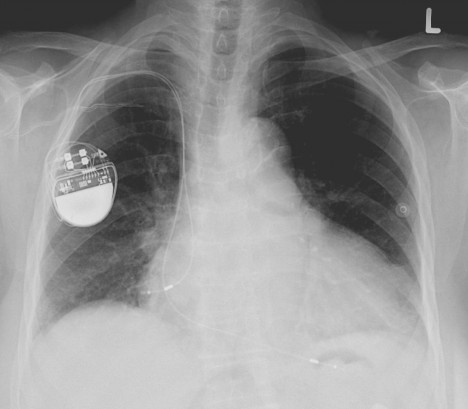

O tři týdny později už Greatbatch nese svůj prototyp elektronického kardiostimulátoru do buffalské nemocnice. Tamější chirurg William C. Chardack jeho vynález implantuje do těla psa, jehož postihla srdeční blokáda.

Už 15. dubna 1960 Chardackův lékařský tým voperuje kardiostimulátor deseti pacientům s úplnou srdeční blokádou. Bez něj by s padesátiprocentní šancí nepřežili ani rok.

První pacient zemře po 18 měsících, jinému ta malá zázračná kovová krabička prodlouží život o třicet let.